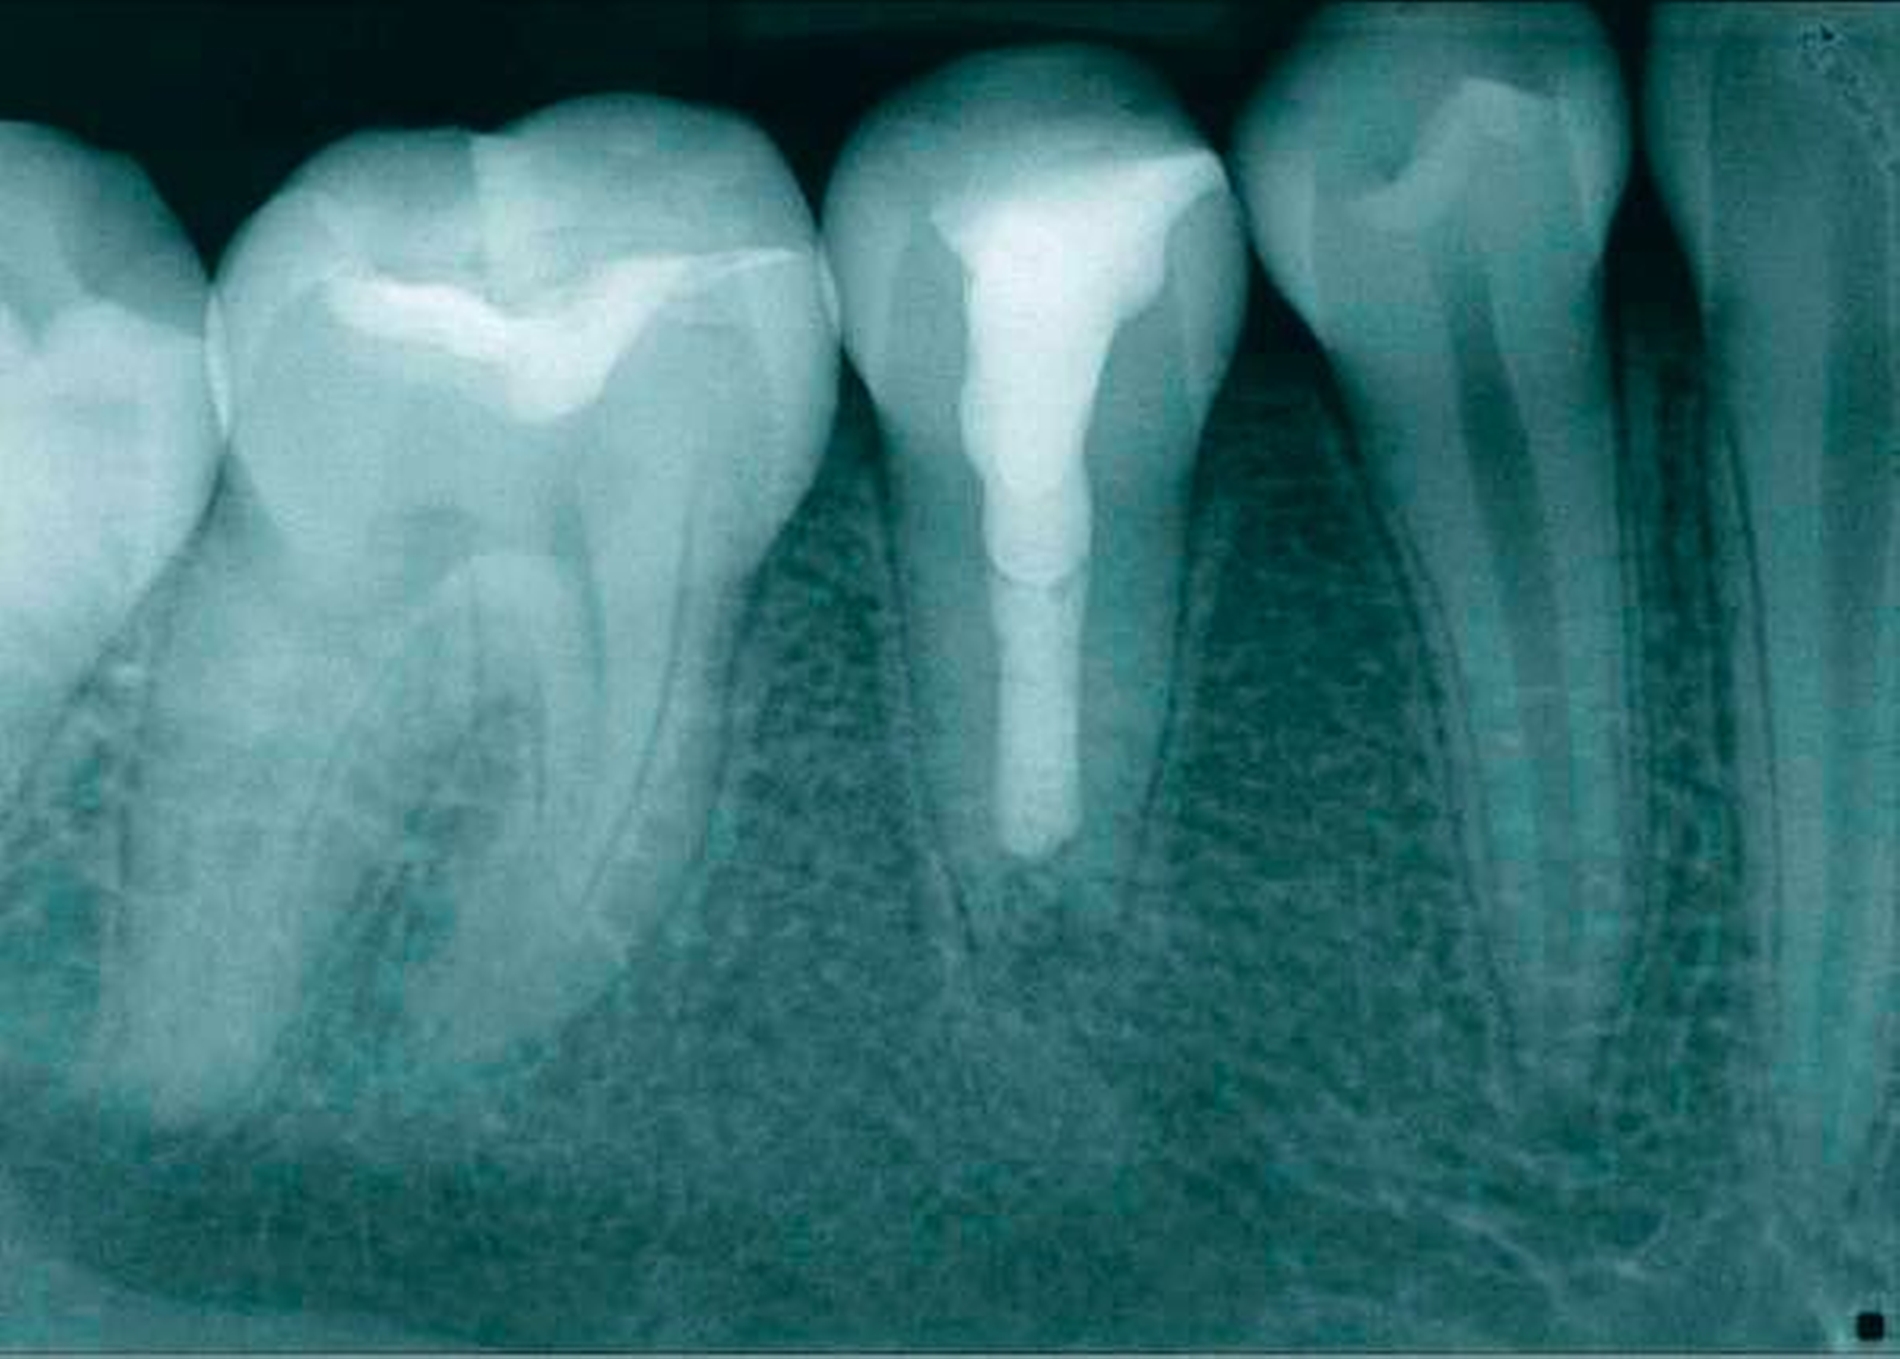

Die zweite Therapiesitzung folgte eine Woche später. Der Fistelgang war bereits ausgeheilt. Nach Spülung mit NaOCl 5 % und EDTA 17 % sowie der Schallaktivierung mittels EDDY (VDW, München) erfolgte die Trocknung des Zahnes. Im Anschluss wurde ein apikaler Verschluss mit weißem ProRoot MTA (Dentsply Sirona, York, PA, USA) appliziert (Abbildung 7). Der Plug wurde auf eine Länge von 15 mm eingebracht – genau der Punkt, ab dem die Patienten das Sondieren wieder gespürt hat. Zur Kontrolle des Plugs erfolgte eine Kontrollaufnahme vor definitivem Verschluss (Abbildung 8).

Anschließend wurde der Rest des Kanals adhäsiv verklebt und indirekt mit Komposit versorgt. Eine Kontrollaufnahme wurde angefertigt (Abbildung 9). Abbildung 10 zeigt die postendodontische Versorgung des Zahnes.